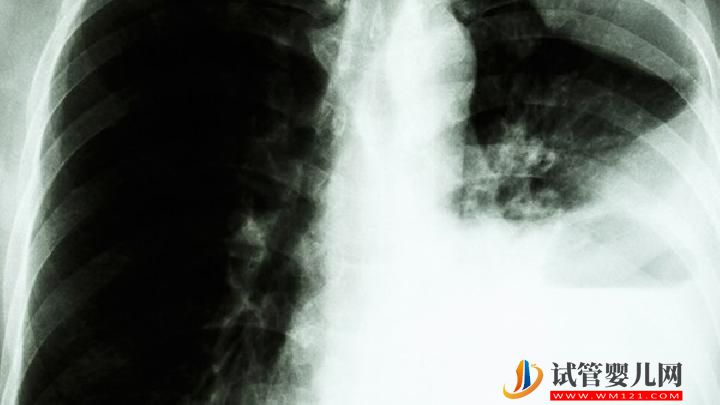

为什么肺癌不传染?

首先,我们应该知道肺癌是一种癌症,它是否是一种传染病,它是否会被感染,然后我们应该找出癌症是否会被感染。这个问题早就被提出了,并进行了大量的观察和研究。